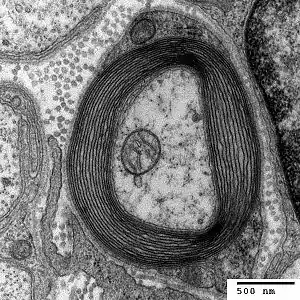

Nerve with myelin sheath

HNPP is caused by a mutation in the gene PMP22, which makes peripheral myelin protein 22. This protein has a role in the maintenance of the myelin sheath that insulates nerves, resulting in insufficient conductivity in the nerves. HNPP is part of the group of hereditary motor and sensory neuropathy (HMSN) disorders and is linked to Charcot–Marie–Tooth disease (CMT).[5]

Myelinated neuron

The condition is caused by a mutation in one copy of the gene PMP22 (peripheral myelin protein 22, located at locus 17p11.2). This makes it autosomal dominant.[8] PMP22 is involved in maintaining the myelin sheath that surrounds nerves to facilitate conductivity.[5] The mutation causes haploinsufficiency, where the activity of the normal gene is insufficient to compensate for the loss of function of the other gene.[9]

The peripheral myelin protein 22 gene encodes a 22-kD protein that comprises 2 to 5% of peripheral nervous system myelin.[10]